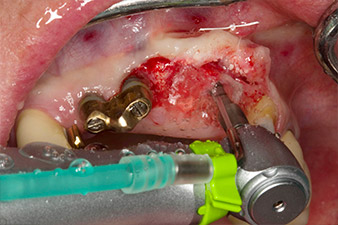

initial radiological findings

Fig. 1: The initial radiological findings revealed a splinted crown restoration requiring replacement. When the restoration was removed, teeth 21 and 22 were unintentionally extracted along with it.

The x-ray revealed horizontal bone loss around teeth 21 and 22 (Fig. 1). When the crown block was removed, these teeth were unintentionally extracted with it.